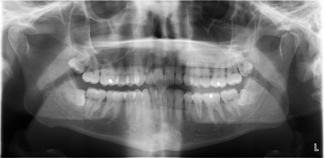

På Ortopan (OTP) panorama-røntgenbilledet fra 2009 kan I se tænderne. Allerede på det tidpsunkt ville de opere samtlige visdomstænder ud af af mind mund. Jeg skiftede tandlæge og fik en anden vurdering.

Et besøg hos tandlægen i slutningen af November 2014 viser, at det er tiden er kommet til at fjerne de vandretliggende visdomstænder i min mund - der er kommet hul (caries), da de har brudt gennem tandkødet. Jeg har svært ved at børste dem, uden at gøre skade på det omkringliggende tandkød - de ligger også vandret med tandkronen mod kindtanden. Den store udfordring er, at visdomstænderne i den nedre del af kæben ligger i nærheden af nervebanerne. En kirurgisk operation er nødvendig for at fjerne dem og der er risiko for, at jeg mister følelsesevnen i underkæben, hvis de bliver fjernet. Bliver de ikke fjernet, er der risiko for at mine kindtænder bliver ødelagt, på grund af trykket fra visdomstænderne. Den eneste trøst er, at resten af tænderne er i fantastisk form. Tandplejeren spørger om jeg anvender elektrisk tandbørste, hvortil jeg svarer nej. Tandplejeren fortæller, at det er sjældent at tænder kan være så rene uden at anvende en elektrisk tandbørste. Hun går også i gang med at rense tænderne, men konstaterer efter få sekunder, at det ikke er nødvendigt og stopper. Det store spørgsmål er, om jeg er dygtig til at børste tænder, eller om det er min veganske kost og relativt store indtagelse af vand, som holder tænderne i god stand? Det ender med en tandpudsning og en henvisning til en tandkirurgisk afdeling i Århus, som kan fjerne mine visdomstænder i underkæben.